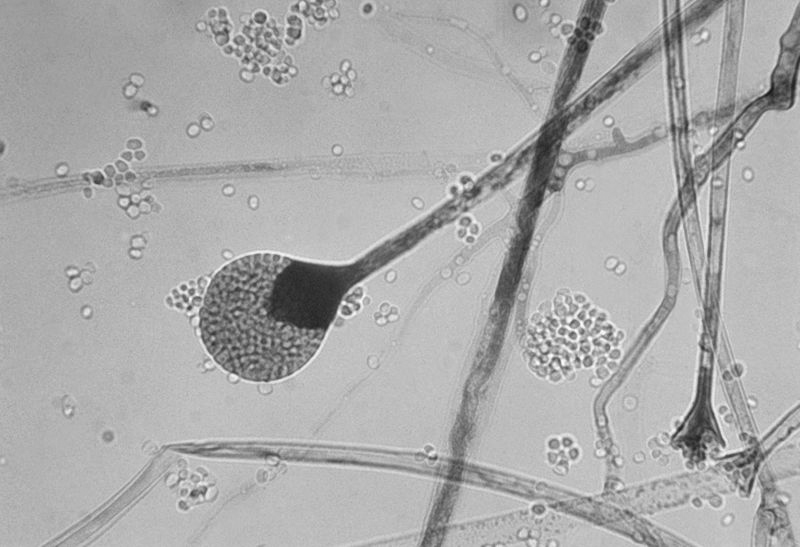

ब्लैक फंगस या काली फफूंद सामान्यत: बासी रोटियों, ब्रेड, सड़े-गले पदार्थों, चमड़े की चीज़ों, गोबर, मिट्टी और नमी वाले स्थानों पर पाई जाती है। कवक विज्ञान की दृष्टि से ये ज़ायगोमाइकोटिना समूह की सदस्य हैं जो मुख्य रूप से मृतोपजीवी हैं (यानी सड़ते-गलते पदार्थों से पोषण प्राप्त करती हैं)। अपवादस्वरूप ये दुर्बल परजीवी की तरह व्यवहार करती हैं। इनका शरीर महीन सफेद तंतुओं के जाल से बना होता है और पर्याप्त पोषण और अनुकूल पर्यावरण में ये असंख्य गहरे भूरे या काले बीजाणु का उत्पादन करती हैं। ये बीजाणु ही फफूंद के फैलाव और रोग के कारण बनते हैं।

यह फफूंद रक्त वाहिनी में घुसपैठ करती है और नाक, आंख, फेफड़ों, मस्तिष्क और गुर्दों सहित शरीर के प्रमुख अंगों को नुकसान पहुंचाती है। पूरे विश्व में म्यूकरमाइकोसिस पैदा करने वाली प्रमुख फफूंद राइज़ोपस ओराइज़ी है। इसके अलावा अलग-अलग भौगोलिक क्षेत्रों में इसी वर्ग के म्यूकर सहित 11 वंश और 27 प्रजातियां मनुष्य में संक्रमण का कारण बनती हैं।